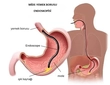

Diş eti yaraları, diş etlerinde meydana gelen iltihaplanma, enfeksiyon veya yaralanma sonucu oluşan rahatsız edici durumlardır. Bu yaralar, genellikle diş eti hastalıkları, travmalar veya ağız hijyeninin yetersizliği nedeniyle ortaya çıkar. Diş eti yaralarının etkili bir şekilde tedavi edilmesi, ağız sağlığının korunması açısından son derece önemlidir. Bu makalede, diş eti yaralarına iyi gelen yöntemler ve önleyici tedbirler ele alınacaktır. Diş Eti Yaralarının Belirtileri Diş eti yaraları genellikle aşağıdaki belirtilerle kendini gösterir:

Sonuç Diş eti yaraları, ağız sağlığını olumsuz etkileyen ciddi bir sorundur. Bu yaraların tedavi edilmesi ve önlenmesi için yukarıda belirtilen yöntemler ve önleyici tedbirler dikkate alınmalıdır. Ağız sağlığını korumak için düzenli diş muayeneleri ve doğru ağız hijyeni alışkanlıkları geliştirmek, diş eti yaralarının önlenmesinde büyük rol oynamaktadır. Unutulmamalıdır ki, diş eti yaralarıyla ilgili şikayetleriniz varsa, bir diş hekimine başvurmanız önemlidir. Ekstra Bilgiler: Diş eti yaralarının tedavisinde kullanılan ilaçların ve doğal tedavi yöntemlerinin etkinliği kişiden kişiye değişebilir. Bu nedenle, herhangi bir tedavi yöntemine başlamadan önce bir sağlık uzmanına danışmak önemlidir. Ayrıca, diş eti sağlığını korumak için düzenli olarak diş doktorunuza gitmek ve önerilen tedavi planlarına uymak gerekmektedir. Diş eti hastalıkları, ilerlediğinde daha ciddi sağlık sorunlarına yol açabileceği için, zamanında müdahale edilmesi gerekmektedir. |